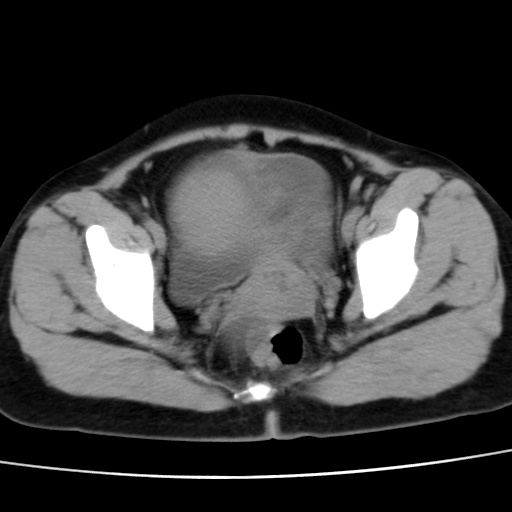

子宫多发肌瘤吗

多发性子宫肌瘤.

考虑多发子宫肌瘤,子宫直肠窝双囊性占位,另直肠周围脂肪密度增高,不知有何病史

支持考虑多发子宫肌瘤~!子宫直肠陷凹积液?

支持考虑多发子宫肌瘤~!子宫直肠陷凹积液!

子宫肌瘤,宫体部后方见液性密度影,是肠道还是子宫与直肠陷窝积液不好说,我觉得它的位置有点高

支持考虑多发子宫肌瘤!子宫直肠陷凹积液!

患者发热,而子宫直肠窝液性灶有明显边缘且局限且囊性,不除外为包裹性积液或脓肿

支持考虑多发子宫肌瘤,子宫直肠陷凹积液可能。

考虑多发子宫肌瘤

1)考虑子宫肌瘤可能性大。2)子宫后方囊性占位性病变,不排除卵巢囊肿可能。

考虑多发子宫肌瘤。子宫后方囊性占位性病变,不排除卵巢囊肿可能。